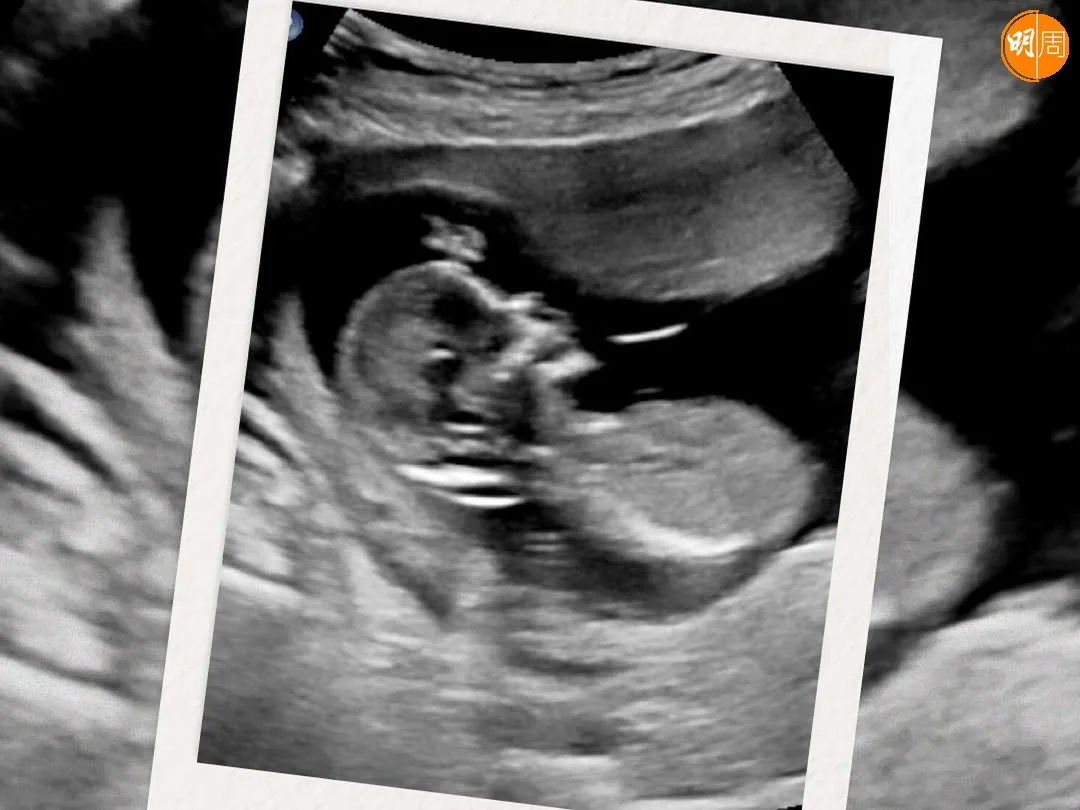

無綫女藝員陳嘉慧(Erica)於2023年10月與圈外男友Calvin結婚,未幾即宣布懷孕,並於翌年三月誕下女兒。昨日(23日),她在社交平台貼出超聲波照片,分享再宣布懷孕喜訊,寫道:「完成咗人生一個小目標三年抱兩,睇吓harper幾開心,做姐姐啦~」她又透露今次的害喜反應,與上次懷孕一樣,「希望呢兩個小怪獸錫住媽咪啦,一大一小都搞到媽咪嘔得好犀利。」